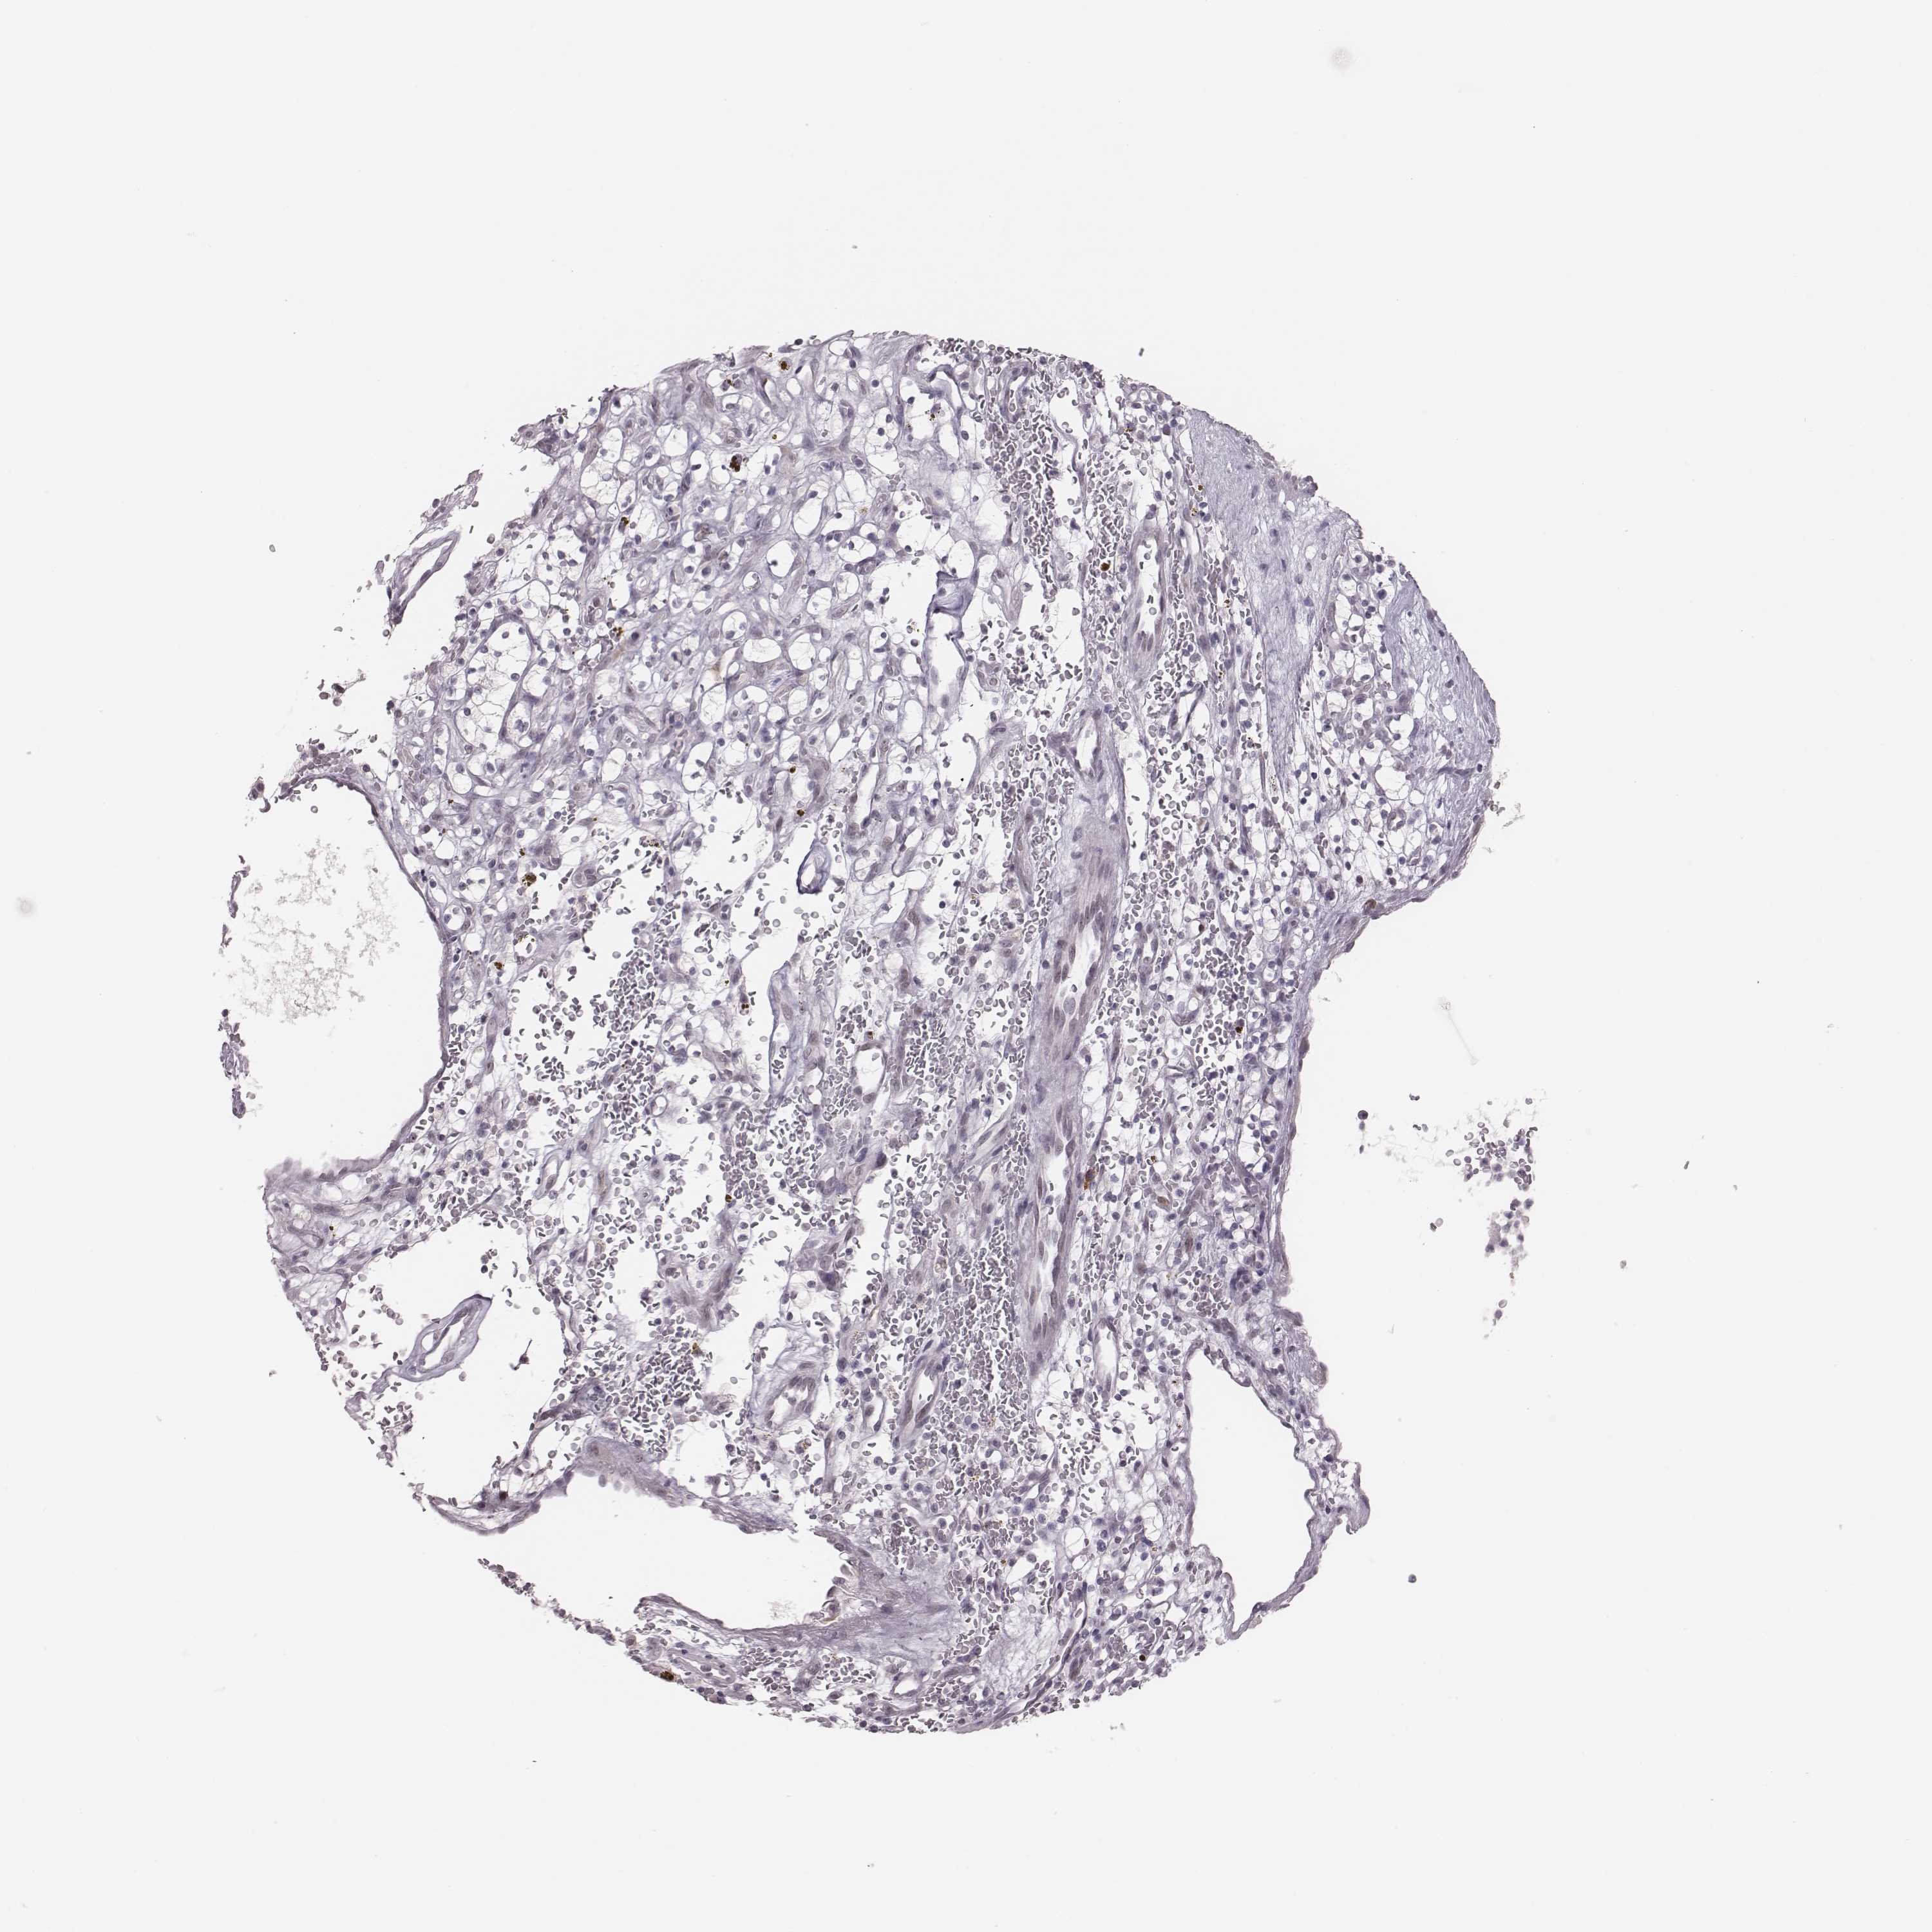

KIDNEY RENAL PAPILLARY CELL CARCINOMA (TCGA) - Interactive survival scatter ploti

The Survival Scatter plot shows the clinical status (i.e. dead or alive) for all individuals in the patient cohort, based on the same data that underlies the corresponding Kaplan-Meier plots. Patients that are alive at last time for follow-up are shown in blue and patients who have died during the study are shown in red.

The x-axis shows the expression levels (FPKM) of the investigated gene in the tumor tissue at the time of diagnosis. The y-axis shows the follow-up time after diagnosis (years). Both axes are complimented with kernel density curves demonstrating the data density over the axes. The top density plot shows the expression levels (FPKM) distribution among dead (red) and alive patients (blue). The right density plot shows the data density of the survived years of dead patients with high and low expression levels respectively, stratified using the cutoff indicated by the vertical dashed line through the Survival Scatter plot. This cutoff is automatically defined based on the FPKM cutoff that minimizes the p-score. The cutoff can be changed by dragging the vertical line or by entering a cutoff value in the square labeled "Current cut-off".

Under the Survival Scatter plot the p-score landscape (black curve; left axis) is shown together with dead median separation (red curve; right axis). Dead median separation is the difference in median mRNA expression between patients who have died with high and low expression, respectively. It is calculated as follows: median FPKM expression of dead patients with high expression - median FPKM expression of dead patients with low expression. This is intended to aid the user in visually exploring custom cutoffs and the associated p-scores and dead median separation.

Individual patient data is displayed and can be filtered by clicking on one or more of the category buttons on the top of the page. Categories describing expression level and patient information include: high, low, alive, dead, female, male and tumor stages. The scale of the x-axis can be toggled between linear and log-scale by clicking on the "x log" button. Mouse-over function shows TCGA ID, patient information and mRNA expression (FPKM) for each patient.

& Survival analysisi

Kaplan-Meier plots summarize results from analysis of correlation between mRNA expression level and patient survival. Patients were divided based on level of expression into one of the two groups "low" (under cut off) or "high" (over cut off). X-axis shows time for survival (years) and y-axis shows the probability of survival, where 1.0 corresponds to 100 percent.

PBK is potential prognostic, high expression is unfavorable in Kidney Renal Papillary Cell Carcinoma (TCGA)

Best expression cut offi

Based on the FPKM value of each gene, patients were classified into two groups and association between prognosis (survival) and gene expression (FPKM) was examined. The best expression cut-off refers the FPKM value that yields maximal difference with regard to survival between the two groups at the lowest log-rank P-value. Best expression cut-off was selected based on survival analysis .